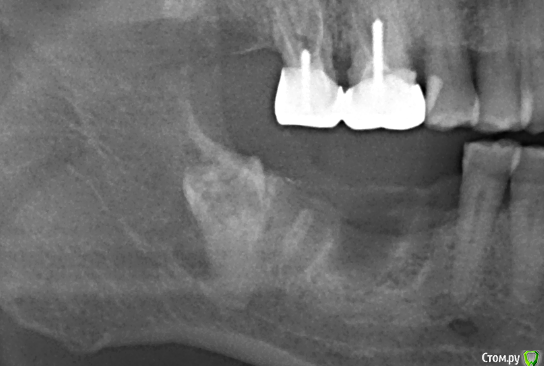

Дмитрий М Опубликовано 16 декабря, 2019 Поделиться Опубликовано 16 декабря, 2019 Коллеги, кто сталкивался? Что произошло с коронкой 8 зуба? полная ретенция, сообщения с полостью рта нет! никогда не беспокоил (пациент и не знал о существовании 8) Ссылка на комментарий

Дмитрий М Опубликовано 18 декабря, 2019 Автор Поделиться Опубликовано 18 декабря, 2019 (изменено) Резорбция или кариес. Удалять планируете?тоже думал кариес, но не кариес 100% резорбцияпланировал удалять, раскрылся и увидел кость в полости зуба, периодонтальной щели нет, как анкилозированный! удалил 6,7,8 не стал, лишняя травма. пульповой камеры нет, зуб мертвый, расти он не будет, имплантации не помешает. Изменено 18 декабря, 2019 пользователем Дмитрий М 2 Ссылка на комментарий